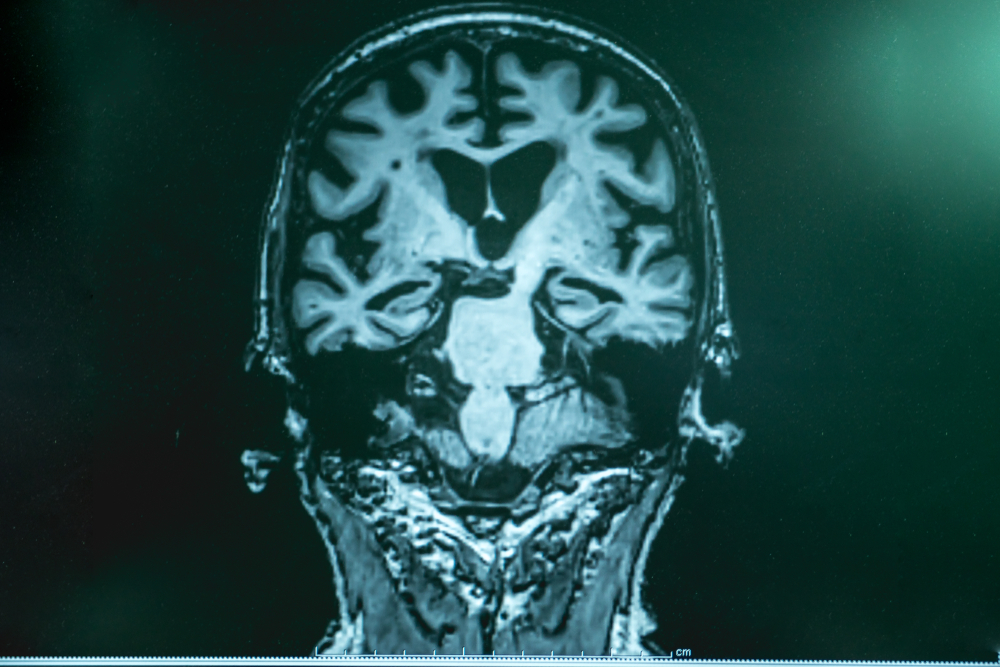

What Alzheimer’s Disease Does to the Brain

Alzheimer’s disease is the leading cause of dementia and accounts for roughly 60 to 80 percent of cases worldwide. It is marked by the buildup of abnormal proteins: beta-amyloid plaques outside neurons and tau tangles inside them. These proteins disrupt communication between brain cells, eventually causing the cells to die. Brain imaging studies show shrinking in the hippocampus and other regions essential for memory and reasoning. Early on, this results in short-term memory loss and difficulty forming new memories. As the disease progresses, it spreads to areas that control language, judgment, and behavior. Alzheimer’s also increases inflammation and reduces blood flow in the brain, worsening damage over time. While current treatments cannot reverse these changes, early recognition helps manage symptoms more effectively.